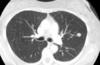

19

A

Patrón intersticial reticular